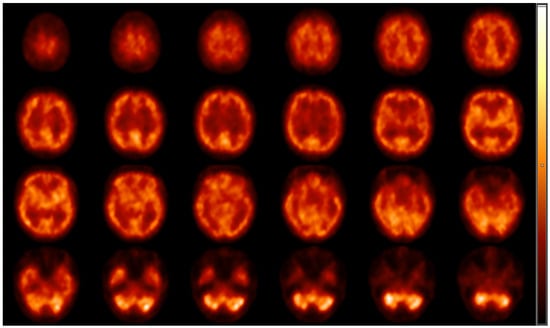

2.6. Brain Perfusion Assessment with Single-Photon Emission Computed Tomography (SPECT) at Rest

- Képes, Z.; Nagy, F.; Budai, Á.; Barna, S.; Esze, R.; Somodi, S.; Káplár, M.; Garai, I.; Varga, J. Age, BMI and diabetes as independent predictors of brain hypoperfusion. Nucl. Med. Rev. 2021, 24, 11–15. [Google Scholar] [CrossRef] [PubMed]

- Willeumier, C.; Taylor, D.; Amen, D. Elevated BMI is associated with decreased blood flow in the prefrontal cortex using SPECT imaging in healthy adults. Obesity 2011, 19, 1095–1097. [Google Scholar] [CrossRef]